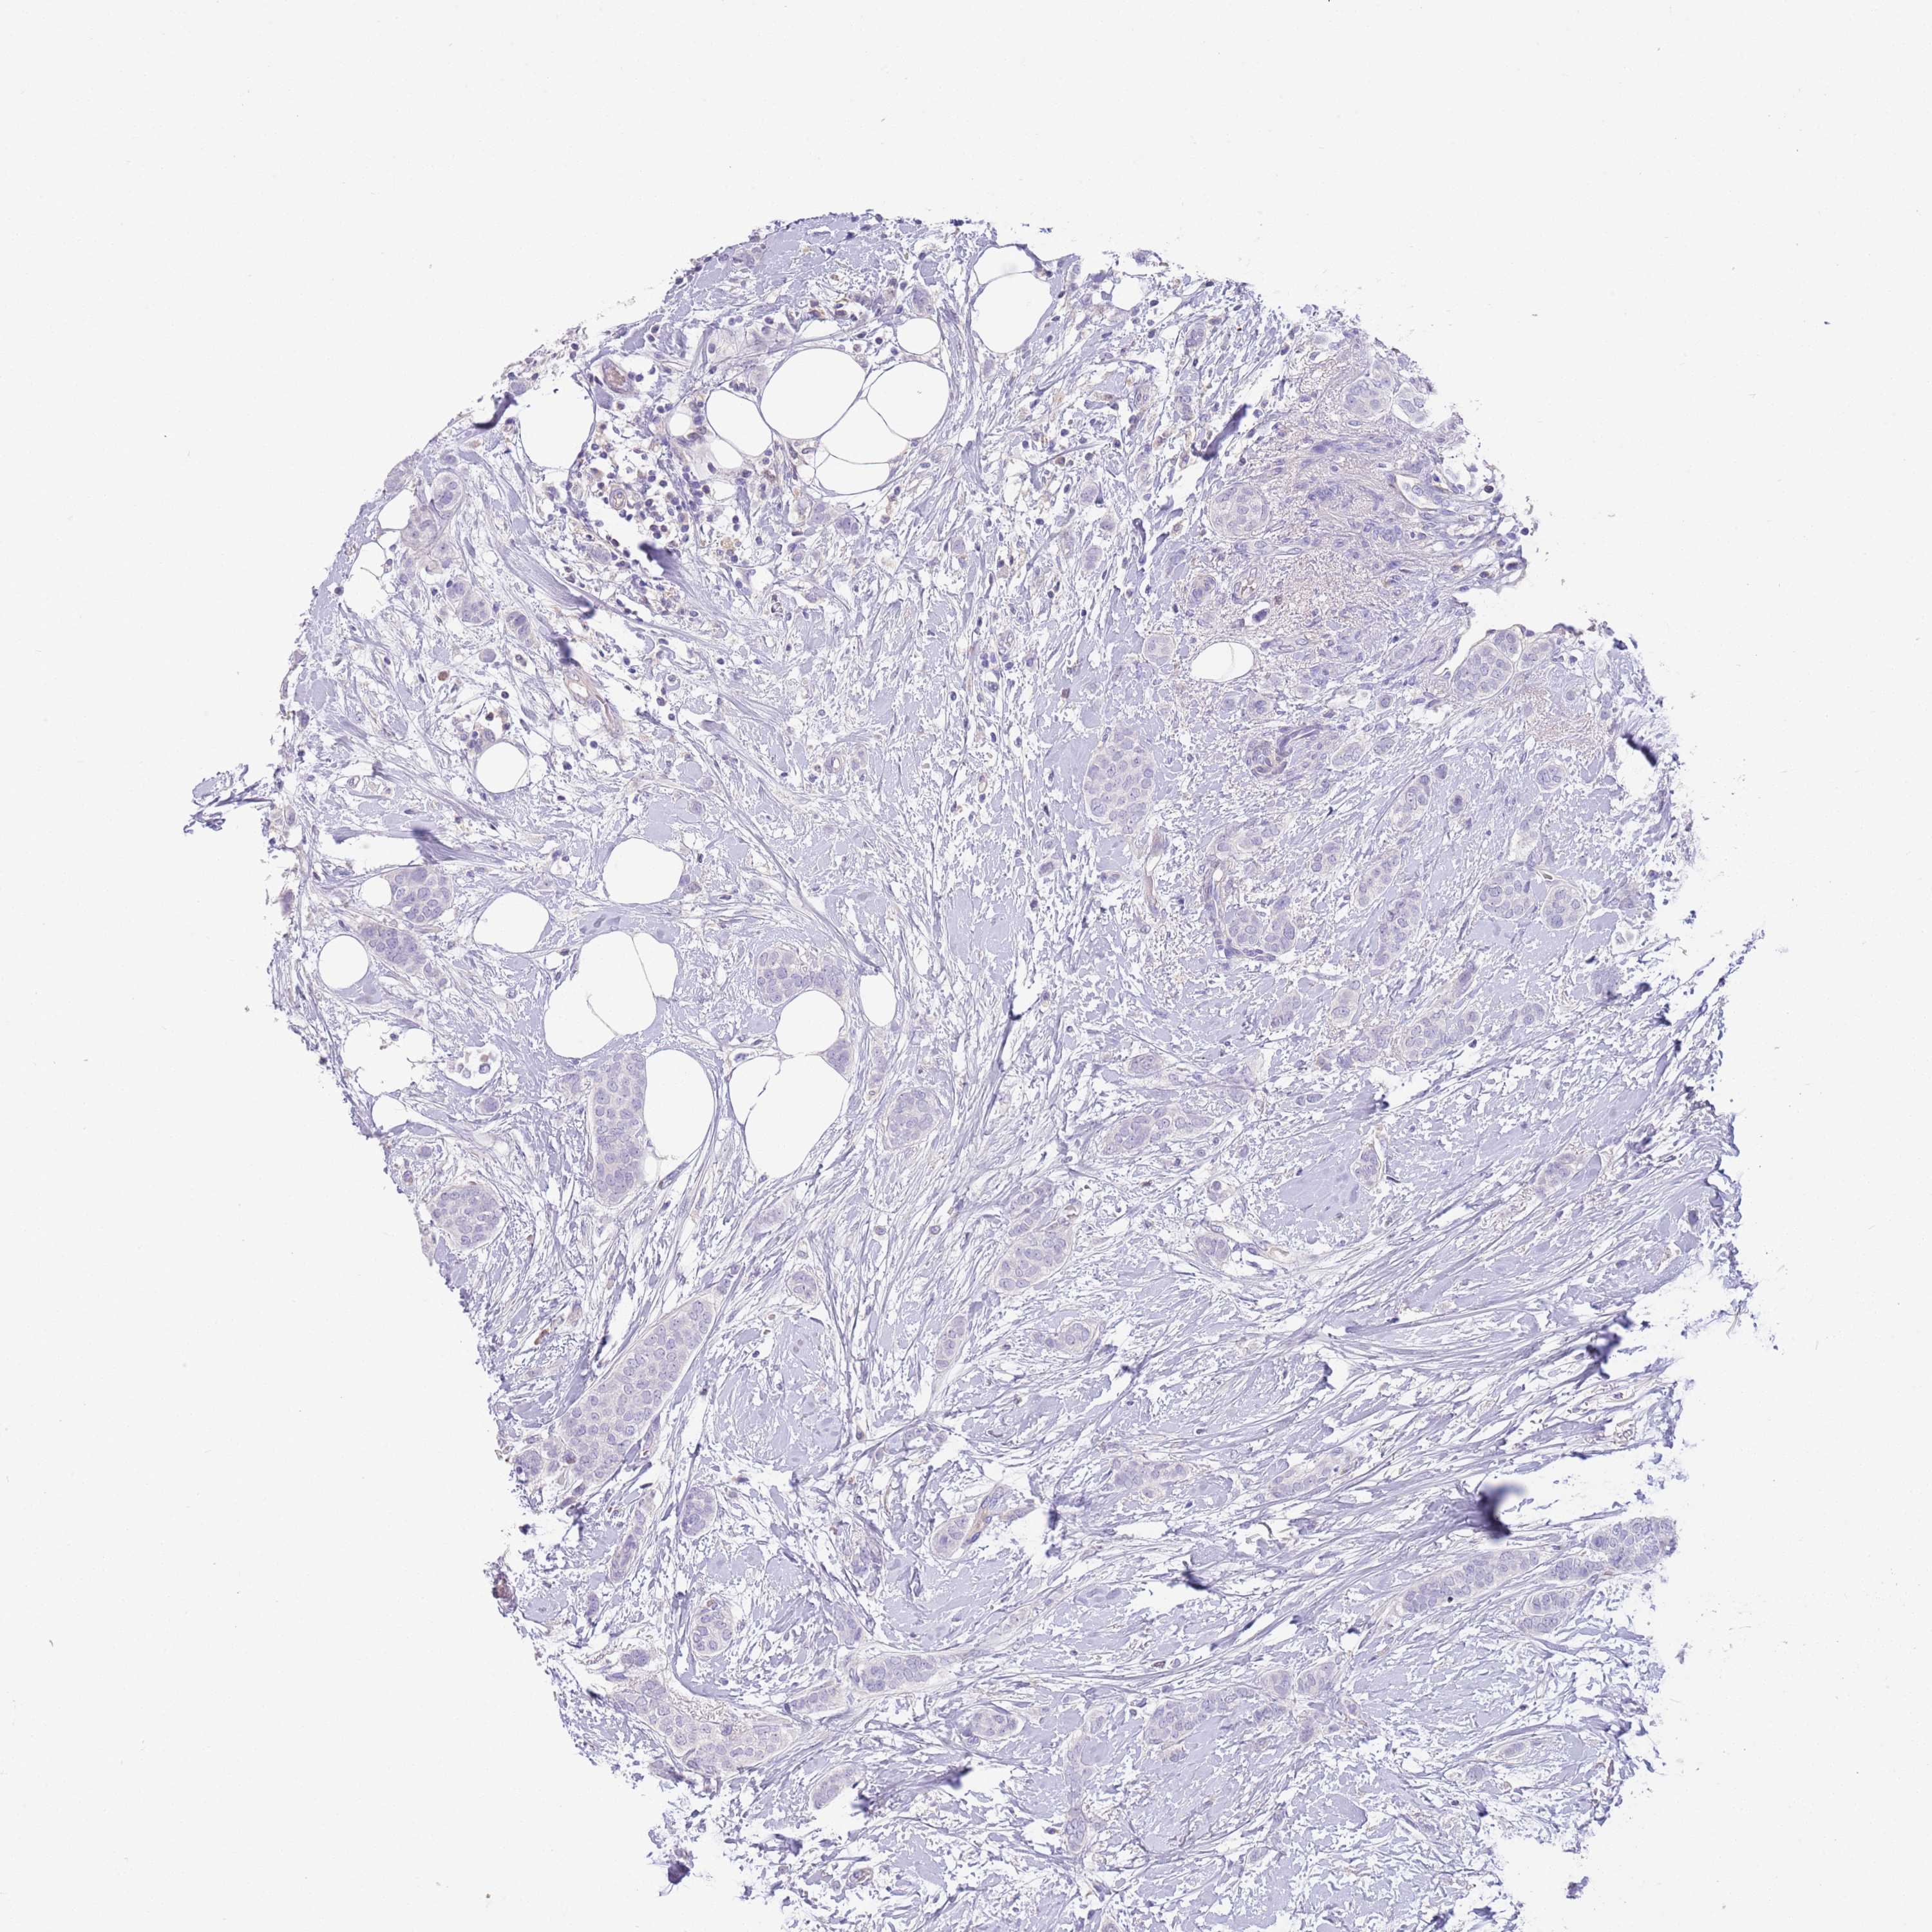

CANCER BREAST CANCER Show tissue menu

BRCA TCGA BRCA VALIDATION PROTEIN EXPRESSION

Breast cancer

Human cancer

Breast invasive carcinoma

IGFL4 is not prognostic in Breast Invasive Carcinoma (TCGA)

TCGA RNA samplesi

RNA-seq data is reported as average FPKM (number Fragments Per Kilobase of exon per Million reads), generated by the The Cancer Genome Atlas (TCGA) .

Normal distribution across the dataset is visualized with box plots, shown as median and 25th and 75th percentiles. Points are displayed as outliers if they are above or below 1.5 times the interquartile range. FPKM values of the individual samples are presented next to the box plot.

Average pTPM 0.4

Number of samples 1022